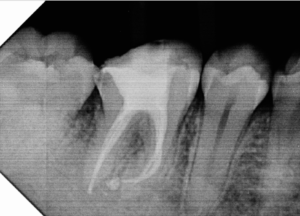

Alguns trabalhos